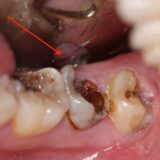

• Xuất hiện vết ố màu nâu hoặc đen: Khi tình trạng sâu răng nhẹ tiến triển, các đốm trắng dần chuyển thành vết ố màu nâu hoặc đen. Đây là dấu hiệu cho thấy men răng đã bị tổn thương nghiêm trọng hơn. Các vết ố này có thể tạo thành các lỗ nhỏ trên bề mặt răng.

• Sâu thân răng: Đây là dạng phổ biến nhất của sâu răng nhẹ. Vi khuẩn tấn công và phá hủy men răng ở bề mặt răng, tạo thành những lỗ nhỏ. Mặt nhai của răng thường dễ bị sâu nhất vì đây là nơi thức ăn dễ bị mắc kẹt.

• Sâu vùng tiếp giáp: Xảy ra ở vùng tiếp giáp giữa răng với răng hoặc răng với mão răng, trám răng. Đây là những vị trí khó vệ sinh, dễ tích tụ mảng bám.